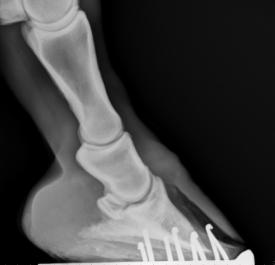

I was called out to this horse as a referral lameness issue. On inspection I found that it had seedy toe. After looking at x-rays the hoof was debrided back to healthy tissue.

In bad cases of seedy toe I always get x-rays taken to see if there has been any changes to the pedal bone for example from infection.  In my experience the only way to treat seedy toe is to remove all necrotic tissue.  When resecting this much hoof wall it is important that you give sole support. On many of these cases the sole is usually prolapsed a little due to the lack of strength in the wall.